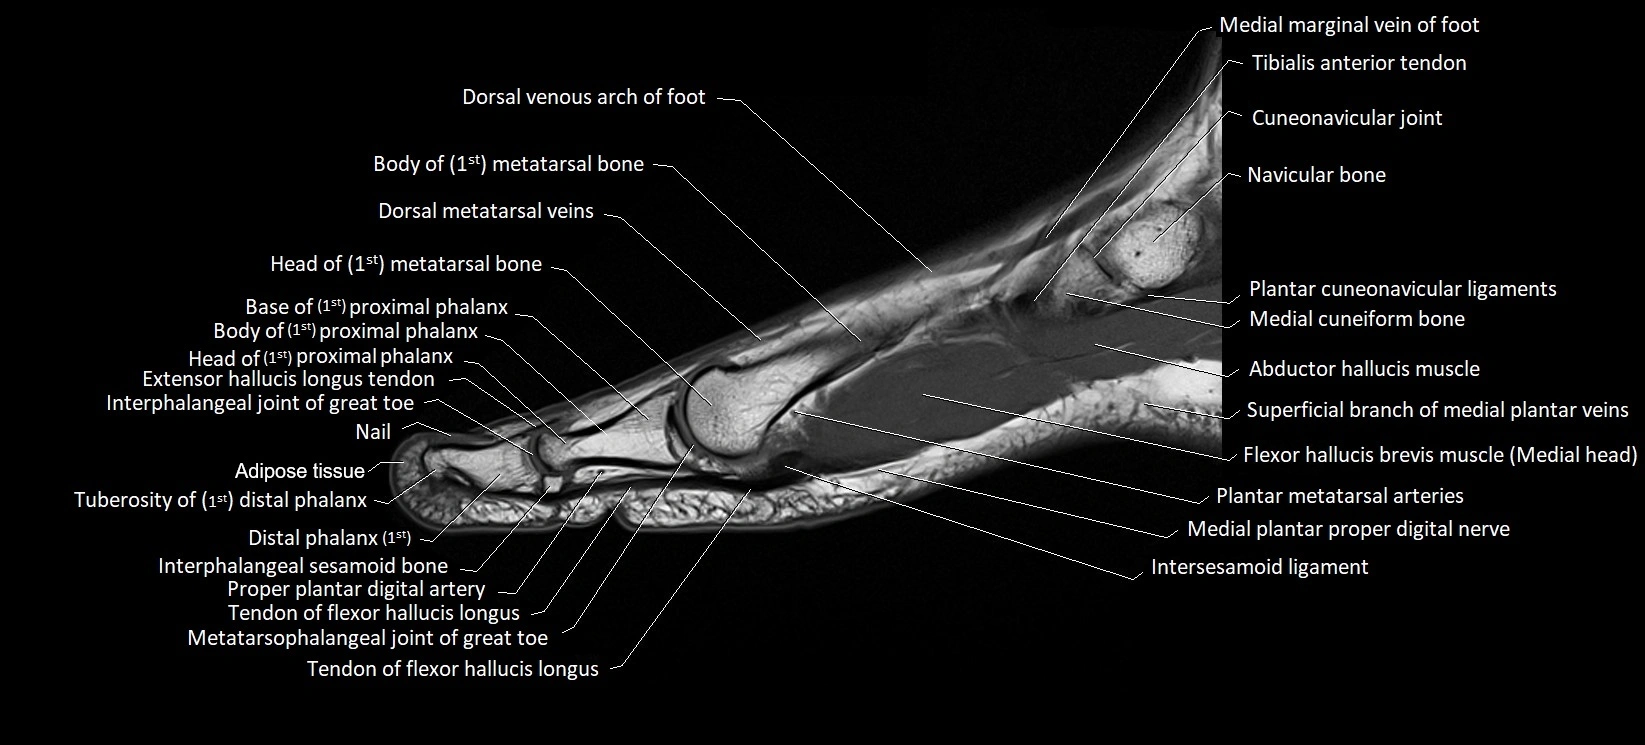

MRI image